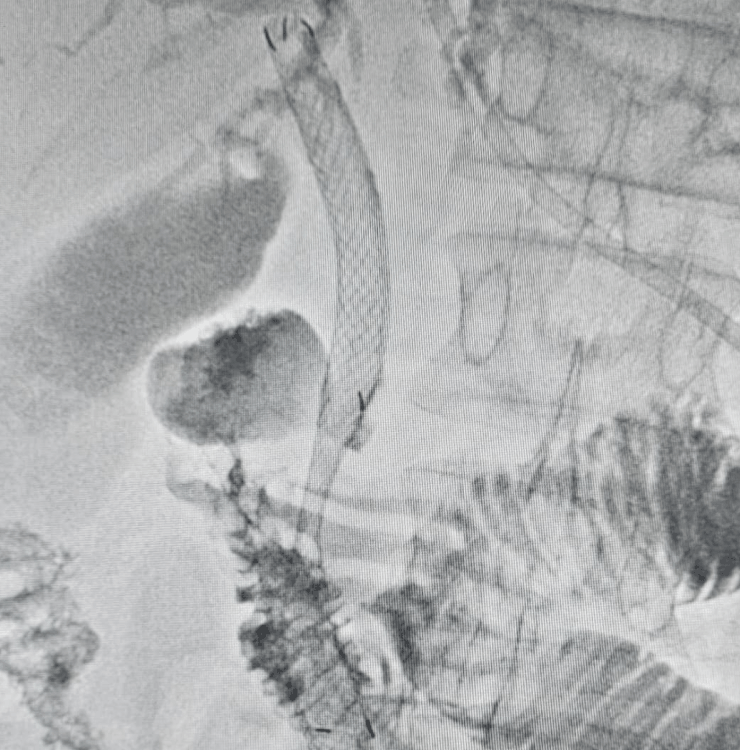

Percutaneous Transhepatic Biliary Drainage (PTBD) and biliary stenting are minimally invasive procedures that use imaging guidance to open blocked bile ducts and divert bile flow, helping reduce jaundice, itching, infection risk and improve overall condition.

PTBD and biliary stenting are performed under ultrasound and fluoroscopy (X‑ray) guidance, usually under local anesthesia with sedation.

- Needle access into a bile duct through the skin and liver using ultrasound and X‑ray guidance.

- Cholangiogram (bile duct contrast study) to identify the exact site and extent of blockage.

- Drainage catheter placement to temporarily drain bile outside or into the intestine (internal–external drainage).